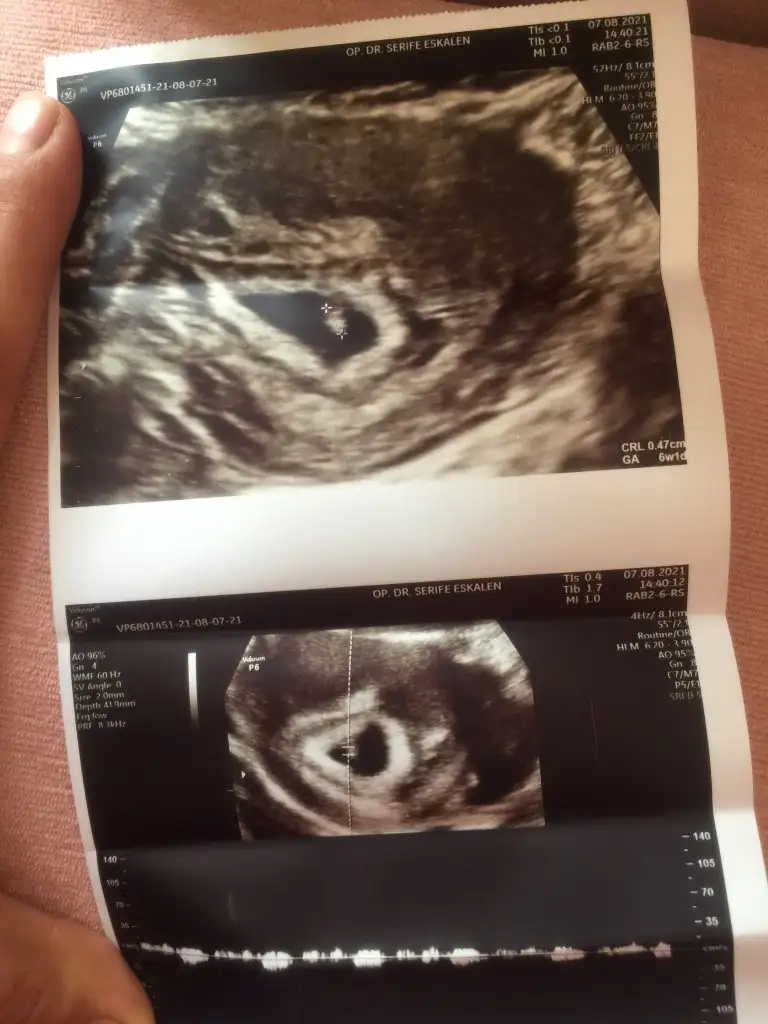

ters rahim durumum var ama 7 haftalık cinsiyet yorumu yapabilir misiniz?

Eklentiler

• BD2896D1-81ED-4160-85A3-442527CBB41F.webp

30,4 KB · Görüntüleme: 421